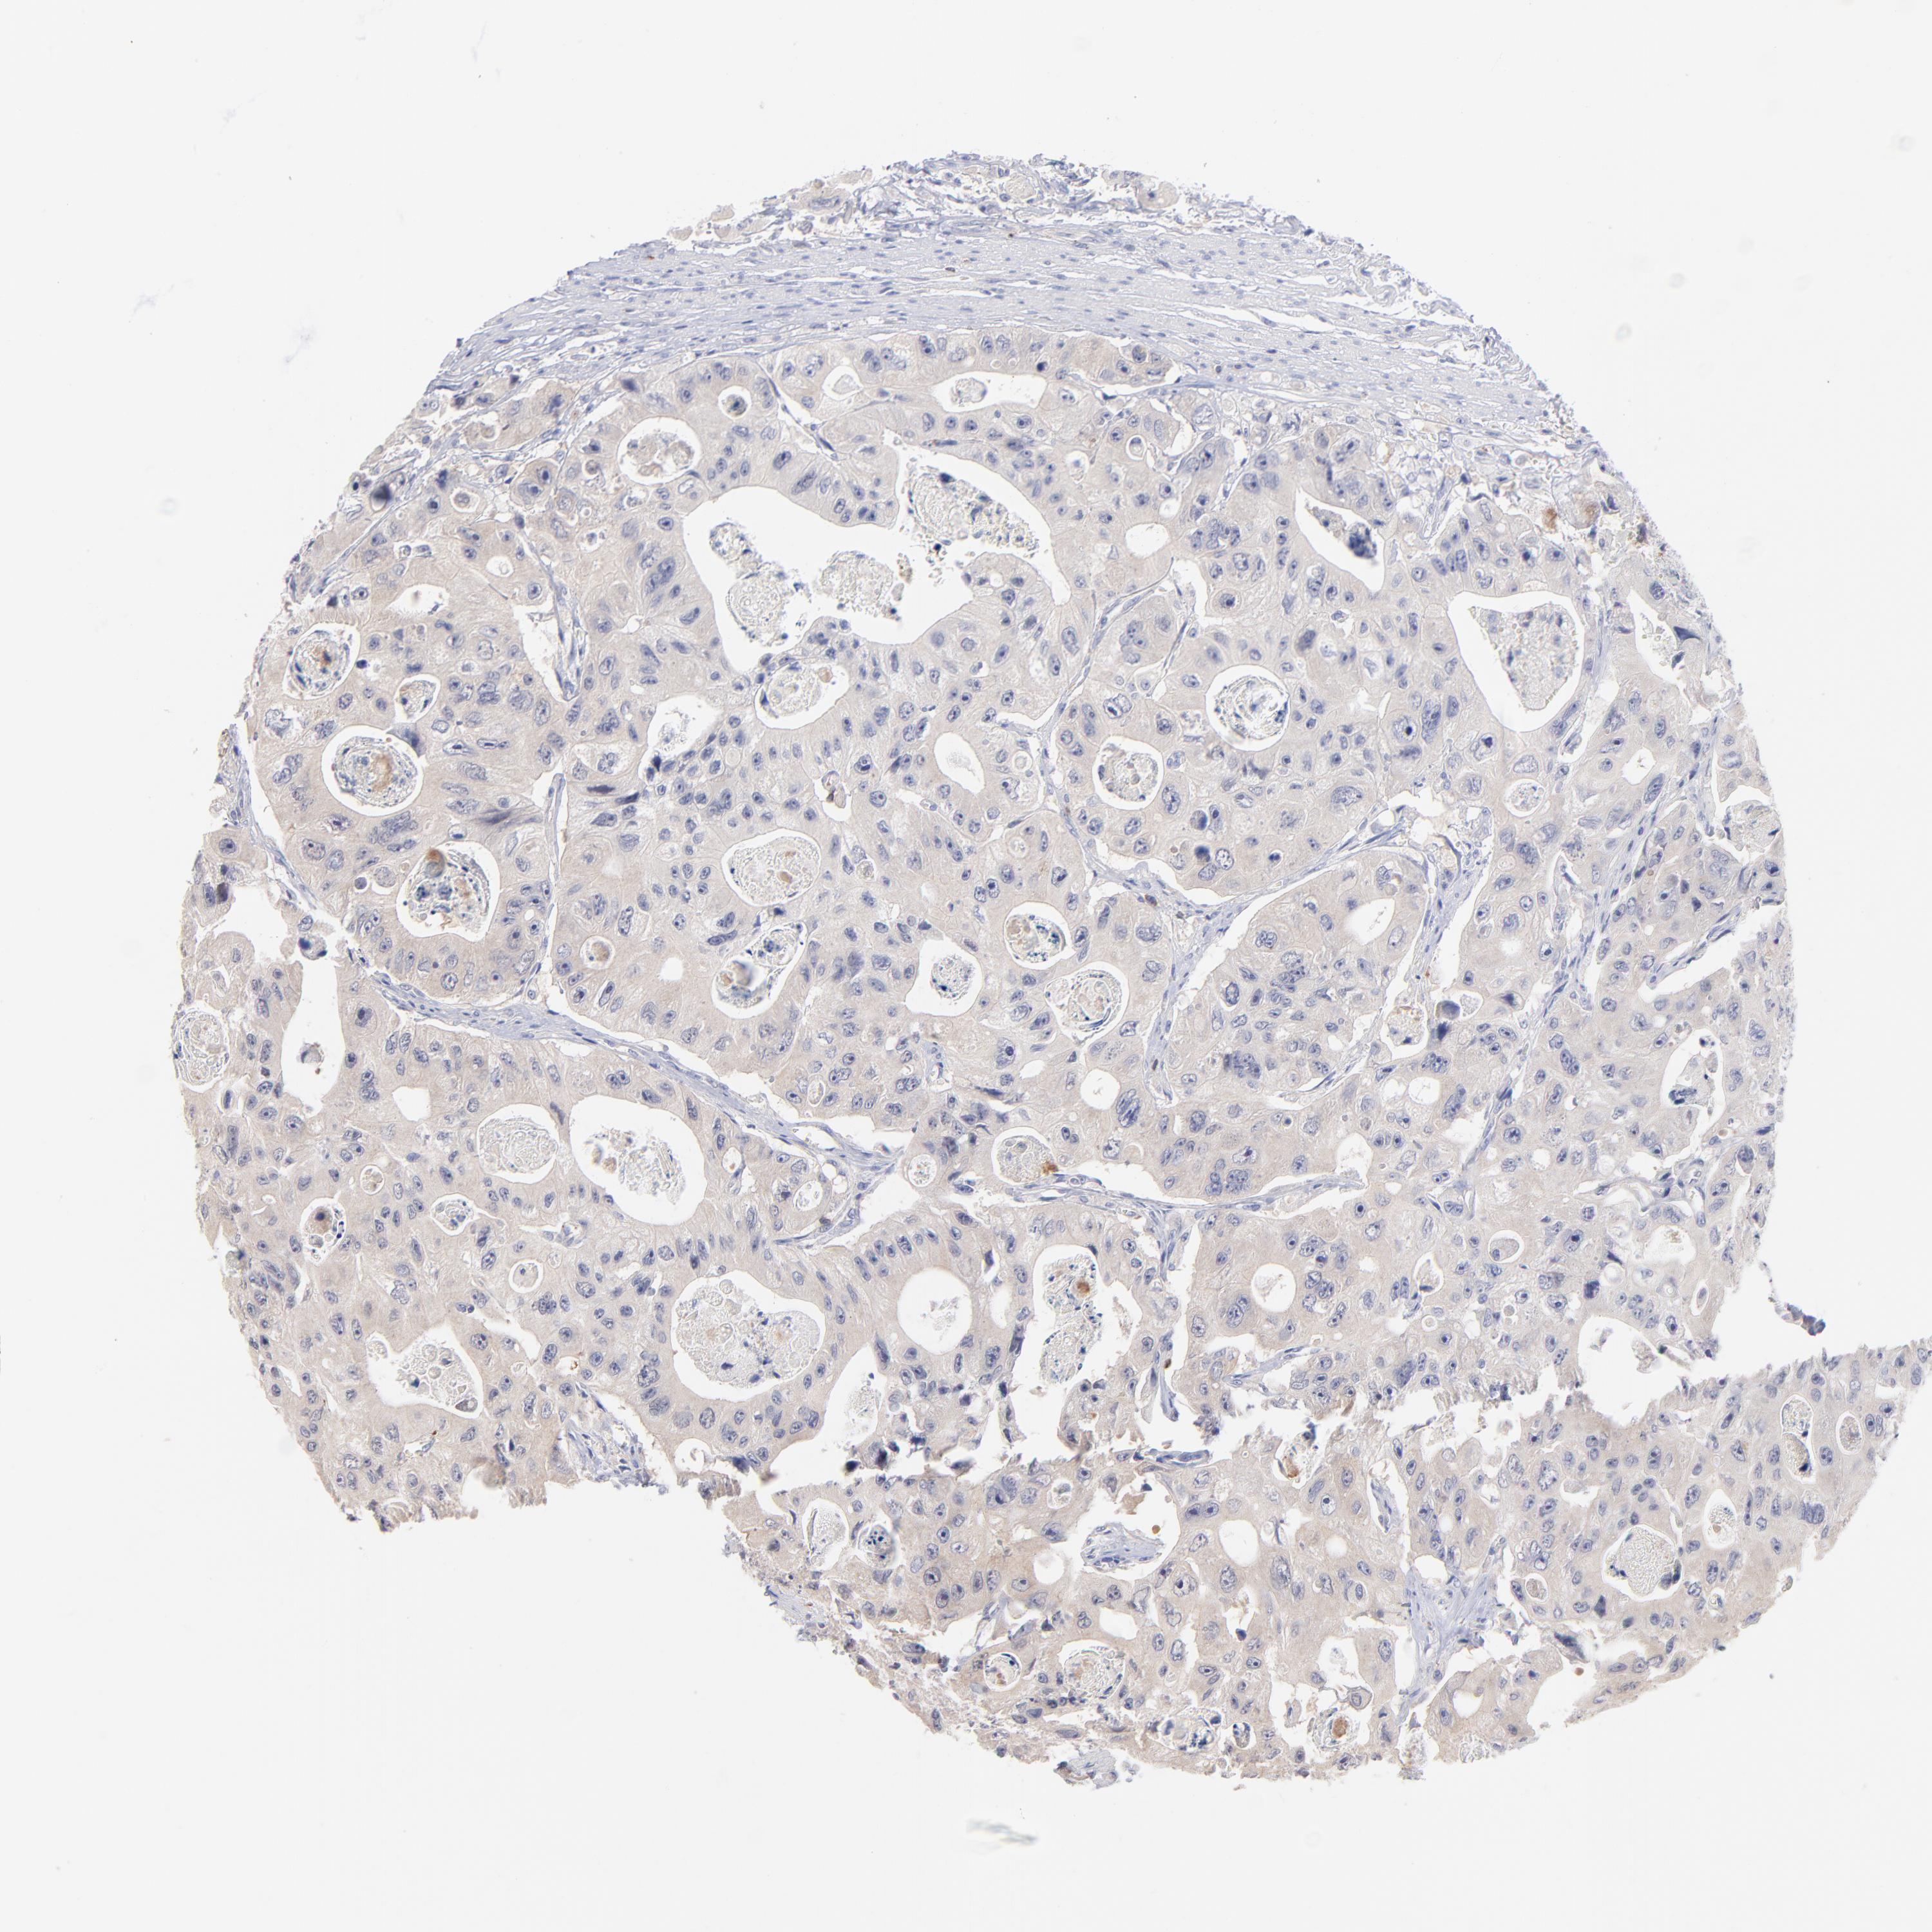

CANCER COLORECTAL CANCER Show tissue menu

Colorectal cancer

Rectum adenocarcinoma

RECTUM ADENOCARCINOMA (TCGA) - Interactive survival scatter ploti

KREMEN2 is not prognostic in Rectum Adenocarcinoma (TCGA)